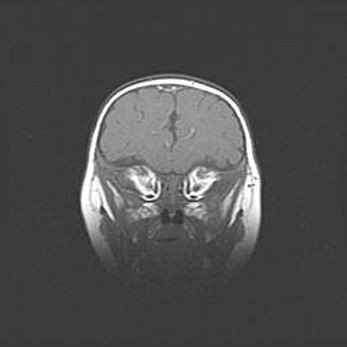

Неполная лизэнцефалия (пахигирия). Открытая гидроцефалия.

Возраст: 17 дней

Вес: 3110 г

Пол: мужской

Окружность головы: 33,5 см

Срок гестации: 35-36 недель

Лизэнцефалия—недоразвитие корковой пластинки и мозговых извилин в результате нарушения миграции нейронов коры. Поверхность мозговых полушарий гладкая. Микроскопически выявляется отсутствие нормальных слоев коры и скопление групп нейронов в подкорковом белом веществе.

Пахигирия—уменьшение числа вторичных извилин. В пораженном полушарии нервные клетки образуют толстый недифференцированный слой с неправильно расположенными нервными волокнами и группами гетеротопных клеток. Нервные клетки незрелые. Белое вещество истончено. При этом нередко аномально развит корково-спинномозговой путь.